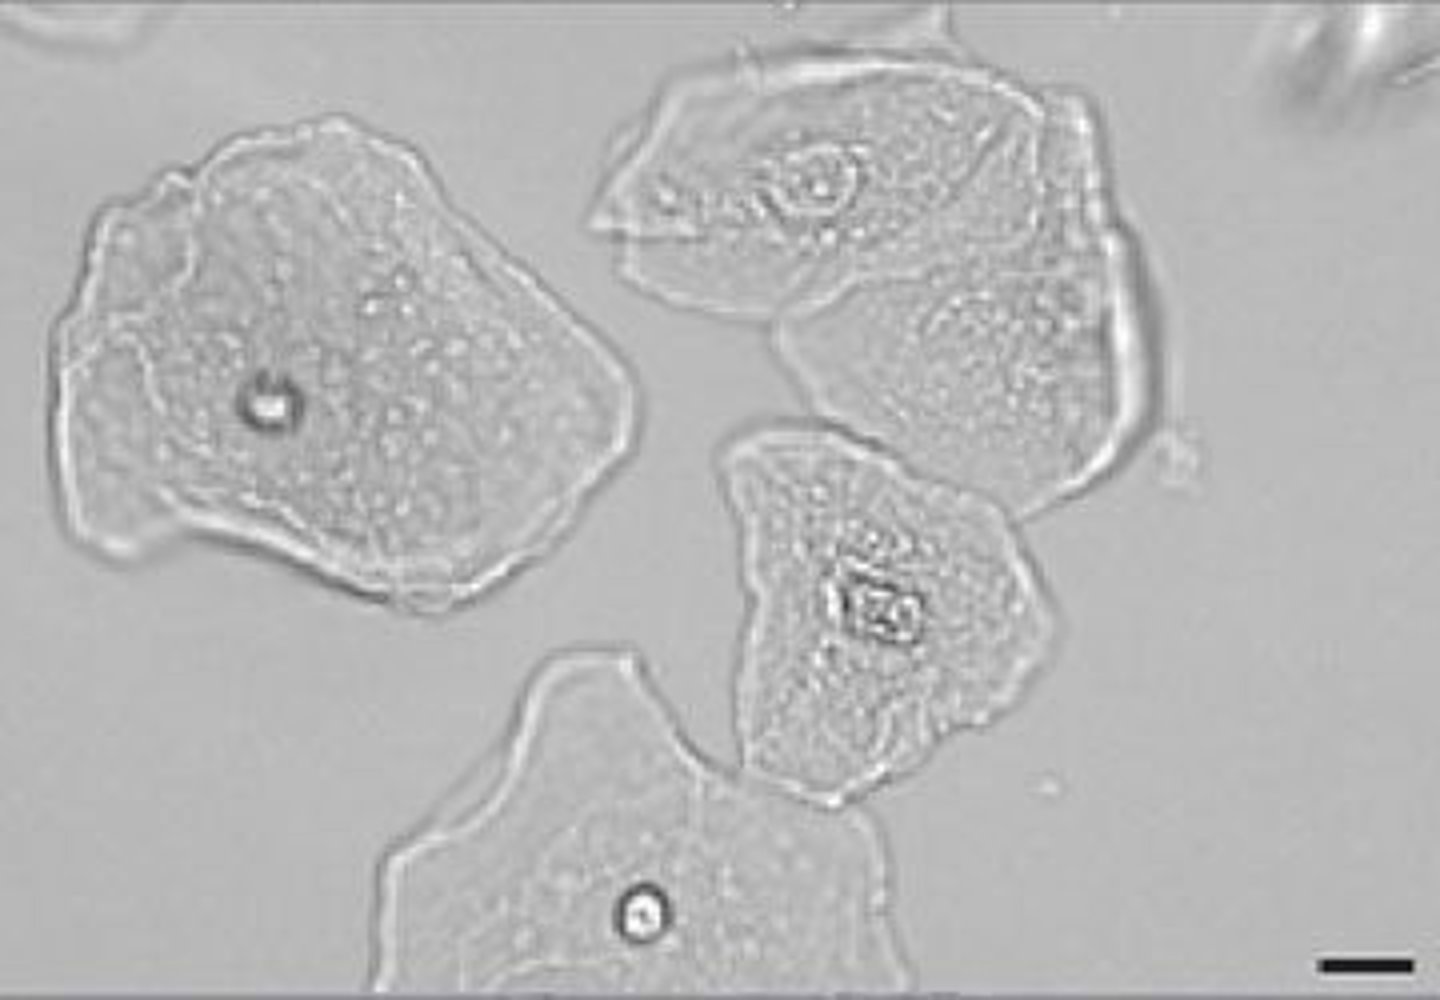

Urine erythrocytes

Leukocytes in urine

spherical, dull gray or greenish yellow; identified by granules or lobes of nucleus

Urine leukocytes

Erythrocytes in fresh urine

small, round, smooth edges

Erythrocytes in older concentrated urine

shrunken and crenate

Erythrocytes in dilute urine

Swollen and lyses

Normal amount of erythrocytes in urine

2-3 RBCs/hpf